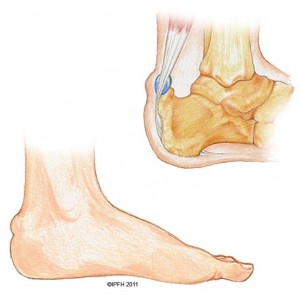

Στα παιδιά γύρω στην ηλικία των 10 ετών συχνότερη αιτία είναι η αποφυσίτιδα της πτέρνας ή νόσος του Sever. Είναι ανάλογη με την αποφυσίτιδα του κνημιαίου κυρτώματος. Προκαλείται από επαναλαμβανόμενες βίαιες έλξεις του αχίλλειου τένοντα πάνω στην οπίσθια απόφυση της πτέρνας.

Νόσος του Sever – αποτελεί τη συχνότερη αιτία πτερναλγίας στα παιδία

Κλινική εικόνα: Η πάθηση εκδηλώνεται με πόνο στο οπίσθιο κάτω μέρος της πτέρνας και ελαφρού βαθμού χωλότητα. Υπάρχει τοπική ευαισθησία στην πίεση.

Τα ακτινολογικά ευρήματα δεν είναι καθόλου ενδεικτικά, γι” αυτό η διάγνωση θα στηριχθεί κυρίως στην κλινική εικόνα. Η αύξηση της πυκνότητας και ο κατακερματιομός του πυρήνα της οπίσθιας απόφυσης της πτέρνας μπορεί να αποτελεί φυσιολογικό εύρημα και μόνο σε σύγκριση προς την άλλη πτέρνα πρέπει να αξιολογείται.

Θεραπεία: Συνήθως δε χρειάζεται ιδιαίτερη θεραπεία. Ανύψωση του τακουνιού του υποδήματος κατά 1 -2 εκατοστά βοηθά στην υποχώρηση των ενοχλημάτων. Σπάνια χρειάζεται γύψινος επίδεσμος. Σε δεύτερο στάδιο φυσικοθεραπείες για διάταση του γαστροκνήμιου-υποκνημίδιου μυός μπορεί να βοηθήσουν στην αποφυγή παρόμοιων επεισοδίων στο μέλλον.